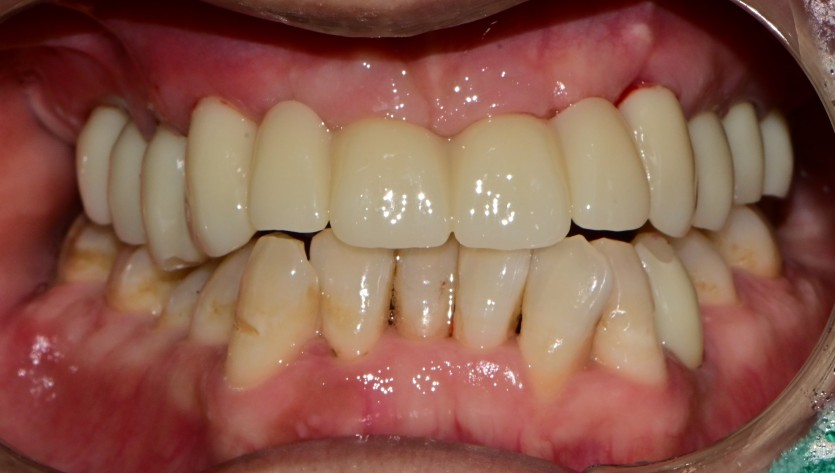

상악 전체 임플란트 증례입니다.

10개의 임플란트로 완성하였습니다.